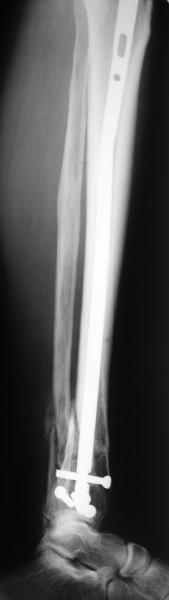

I am just trying to illustrate that prevention of 1)tibial valgus and 2)loss of reduction can be provided without fibular plating. Small changes of conventional nailing techniques allow to maintain reduction of the tibia reliably without adjunctive fibular stabilization.

In delayed cases acute length restoration performed only in the tibia may leave the fibula shortened thus change the mortise. So it is reasonable to restore length of both bones simultaneously by distractor and fix the fibula not with open reduction and plating but just by a single perQ screw. Example attached.

[ Ответить ]